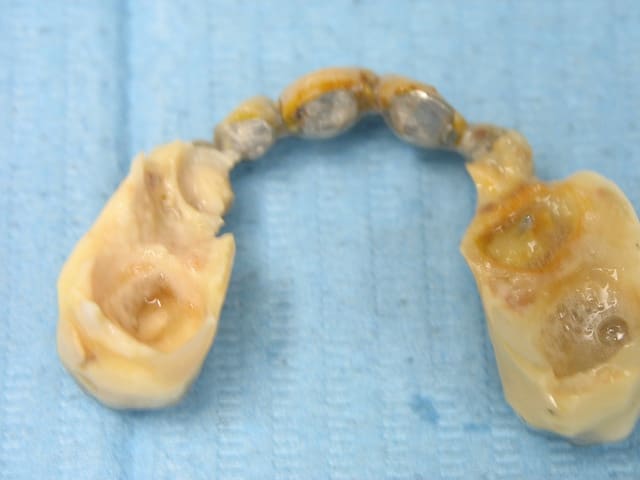

recommandé par une patiente... son amie...

la bridge "amovible"... "réparé au centre médical"...

motif de la consultation: "une infection de la dent du fond" commencée à traiter par 1 clamoxyl, en automédication...